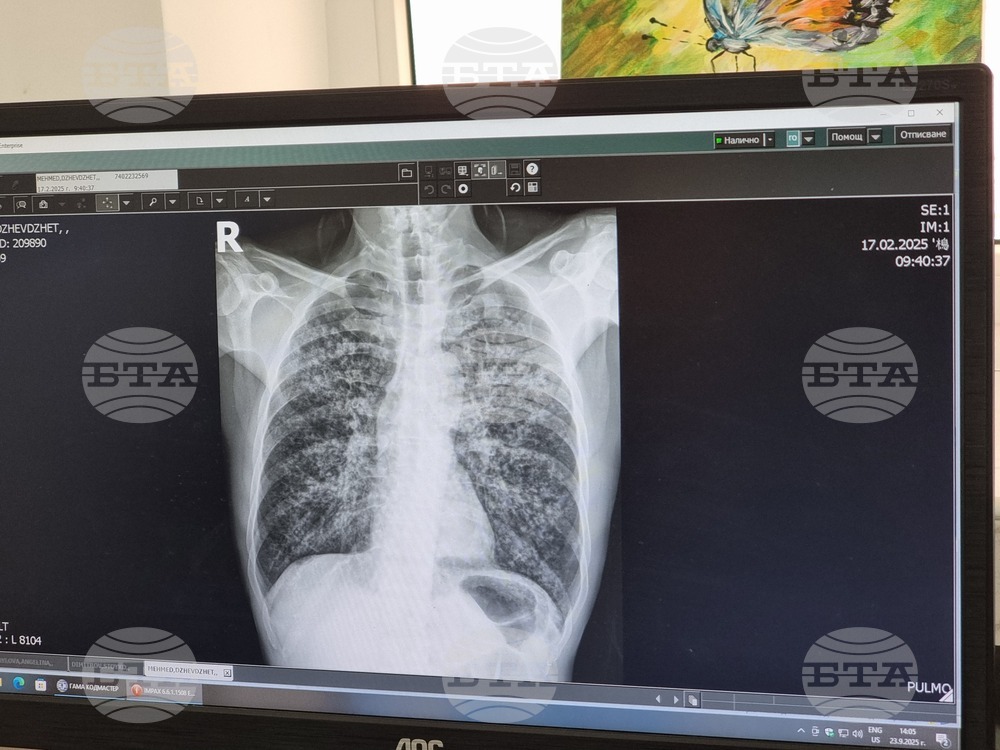

Снимка: кореспондент на БТА в Кърджали Валентина Стоева (архив)

Многопрофилната болница за активно лечение (МБАЛ) „Д-р Иван Селимински-Сливен“ се включва отново в кампанията „Седмица на отворени врати“ за туберкулоза, съобщиха от лечебното заведение. Тя е част от Националната програма за превенция и контрол на туберкулозата в Република България.

В периода от 8 до 12 декември 2025 г. в специализирания кабинет на Отделението по пневмология и фтизиатрия на болницата ще се проведат безплатни прегледи. От 8 до 12 часа ще се извършва скрининг за туберкулоза, прегледи и допълнителни изследвания на съмнителните за болестта лица.